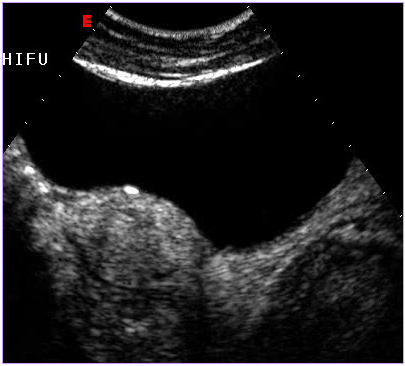

治療后壞死的子宮肌瘤不會消失,而是會發生纖維化,緩慢縮小,但對人體已經沒有危害了。最近,由于磁共振增強掃描(圖1,2)和超聲造影檢查技術(圖3,4)的應用,使治療效果的評價更加客觀和明確。

圖3 治療前超聲造影